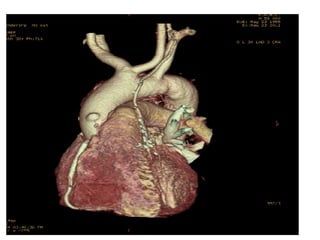

A 60-year-old male with multiple comorbid issues presented to the emergency room with chest pain. An ECG showed tall T waves and right bundle branch block. A CT/PET stress test revealed a small inferolateral infarct and significant peri-infarct ischemia. The patient was referred to cardiology to rule out acute coronary syndrome.